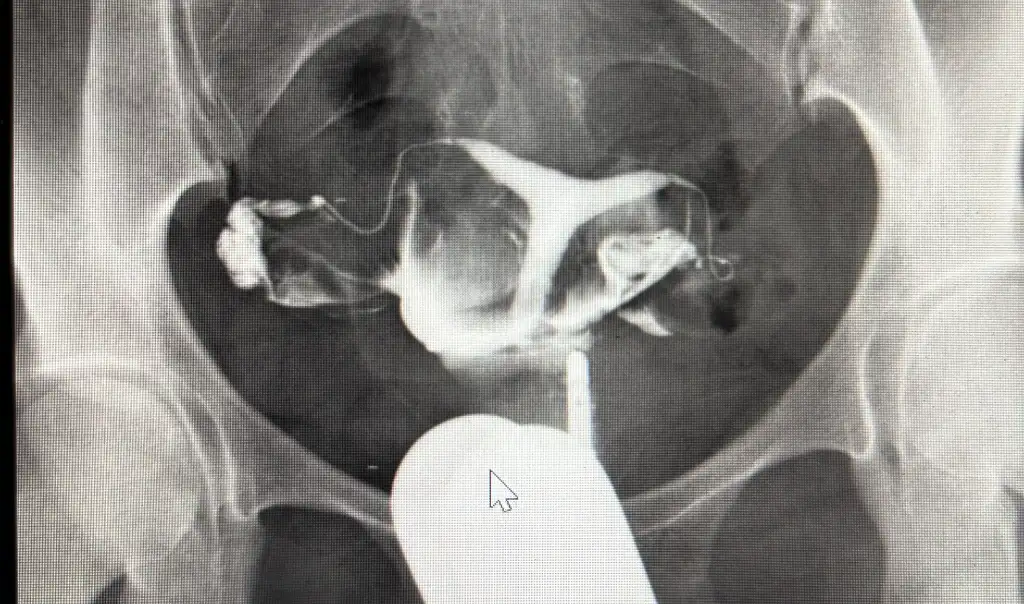

evet verdim pıhtılaşma çıktı fakat son düşüğüm iğneye rağmen düştü bilmiyorum şuan doktorun yanından çıktım y rahimde gerek yok diyor diğer doktor gerekli diyor ne yapıcam bilmiyorum bu gittiğim doktor çok bilgili prof fakat emin olamıyorum sperm testi verecek eşim ona göre tam karar verelim dedi benim filmim aşağıda ekledim bu şekilde

Bende bugün gittiğim doktor öyle dedi kararsız kaldım bunlar düşüğe sebep olmaz rahime dokunmak iyi değil diyor ama sizin rahim t şeklinde mi

Peki rahim duvarına dokunmayalım diyorlar ama başka türlüde engellemenin kesin bir yolunu söylemiyorlar sürekli dene düşük yap kürtaj ol o da rahime müdahale aslında çok işlem görüyor yine aslında bir ihtimal çözümse yaptırmak en doğrusu gibi geliyor benimde rahim filmimde y şeklinde olduğu söyledi 3 düşüğüm var denedim olmadı başka sorunda bulunamadı demekki bunu denemeliyim korkuyorum ama yapacak bişey yok histeroskopi olan arkadaşlar tecrübelerini aktarırsa sevinirim bazılar tıraşlama yapıyorlar 6 ay bekleme süresi oluyor diyorlar forumda biraz ondan dolayı endişe duydum tüpler açıkken biran önce gebe kalmayı istiyorum

Ben ilk düşükten sonra film çektirdim t olduğum anlaşıldı. Düşük bununla alakalı olmayabilir dediler. Bu süreci geçen ağustos ayında yaşadım. Tekrar özel doktora başvurdum. Denememiş söyledi hemen bir sonraki ay tekrat hamile kaldım. Bu sefer 9. Haftafa kalp atışı durdu. İki düşük olunca yine rahimle alakalı olmayabilir dediler. Bütün testleri yaptırdım. Kanpıhtılaşması testinde bir hetorozigotluk çıktı. Başka sorun çıkmadı. Ama yine de histeroskobi olmak istedim. Şuan üzerinden 4 ay geçti gebelik yok. İlk regleden sonra denemeye başladık. Bakalım gebelik ne zaöan olacak. Ama bu tip durumlarda net bir şey söyleyemiyorlar. Bana da düzeltme işlemine gerek yok diyenler oldu. Ama ben artık risk almak istemedim. 3. Gebelikte belli olacak. Bu arada aspirin kullanmaya başladım.

İlk hsg nizin resmi var mı sizde? Yani t rahminizin?

Benim sonuçlarım böyle.

Rica etsem hsg raporunuzu da koyar mısınız? Sizin ve kendi rahim şeklimi chat gbt ye yükledim. Sizin rahminizde yapışıklık olduğunu iddia etti. Sizden istemememin sebebi acaba benimde gerçekten histereskopiye ihtiyacım var mı bunu merak ediyorum

Bende kendi kullandığım uygulamada sordum herhangi bir problem olmadığını söyledi. Aynı program yani sizinkilyle